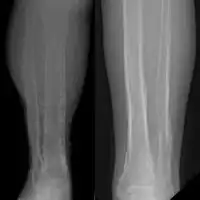

Periosteal reaction from venous stasis